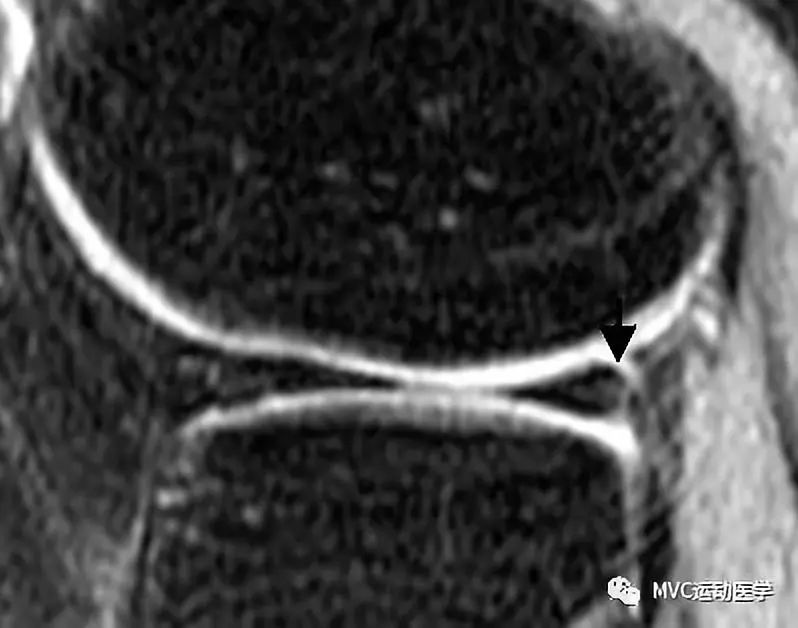

半月板游离缘磨损(黑色箭头)

纤维化的半月板形态正常。如果半月板形态异常(如离断或缩短),则考虑撕裂(放射裂或瓣状裂)。